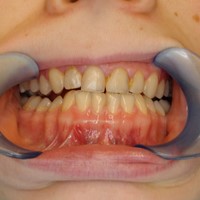

Odbudowa kosci wyrostka zębodołowego żuchwy, odbudowa dziąsła, wydłużenie koron klinicznych górnych przedtrzonowców, implantacja.